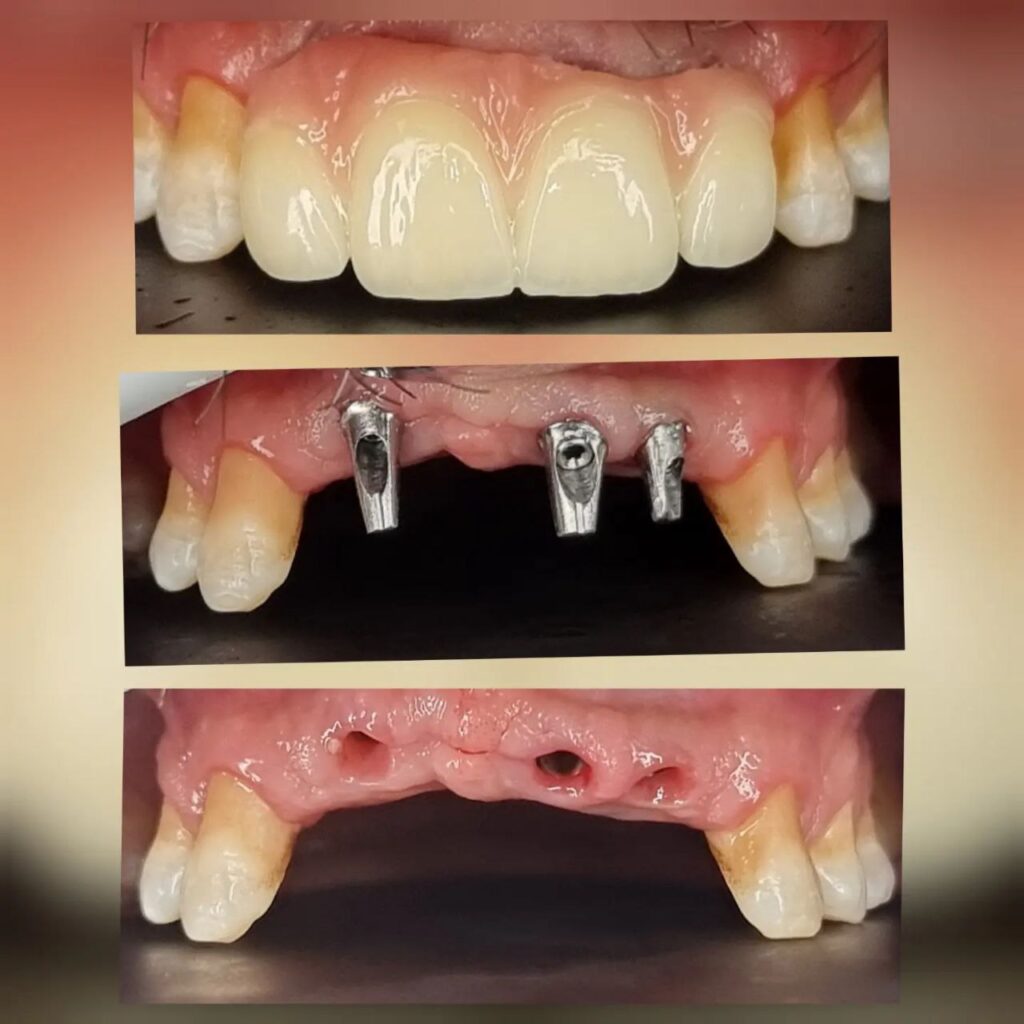

کاشت ایمپلنت دندان

اطمینان حاصل کردن از اینکه دندانهایتان به نحوی زیبا و طبیعی جایگزین شدهاند، از اهمیت بسیاری برخوردار است. ایمپلنت دندان به عنوان یک روش درمانی دائمی در دندانپزشکی شناخته میشود که حاصل آن، یک دندان زیبا و طبیعی در دهان شما خواهد بود.

هرچند که این روش درمانی هزینهی بیشتری نسبت به روشهای دیگر دارد، اما ارزش زیبایی که ایجاد میکند، قابل انکار نیست. ایمپلنتها به قدری شبیه به دندانهای طبیعی هستند که به سختی میتوان آنها را از دیگر دندانها تشخیص داد.